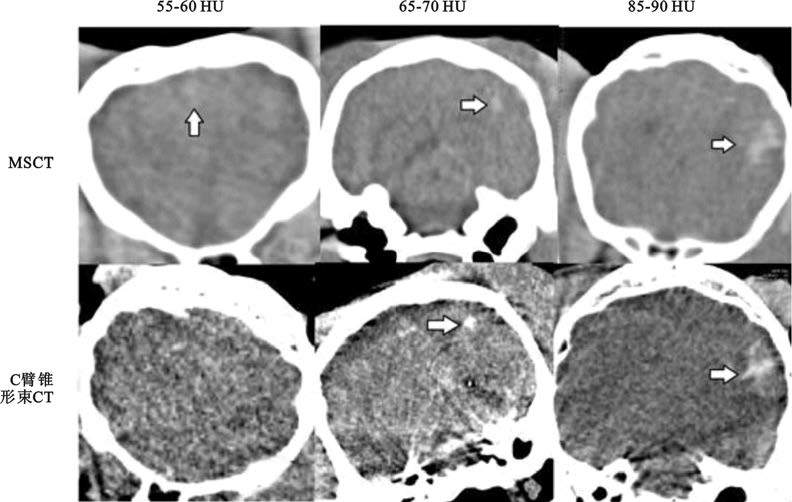

2.2.2?MSCT與C臂錐形束CT兩種成像技術對不同密度血腫的成像質量評分比較差異具有統計學意義(P<0.05)。如圖 1所示,血腫密度在85~90 HU時,兩種技術均能完整清晰地顯示出血腫;隨著血腫密度的降低,C臂錐形束CT的主觀評分呈遞減趨勢。如表 1所示,血腫密度低于65 HU時,C臂錐形束CT成像下血腫顯示不清(評分均值2);血腫密度高于65 HU時,兩種技術對血腫的顯示效果均較好(評分均值≥2)。